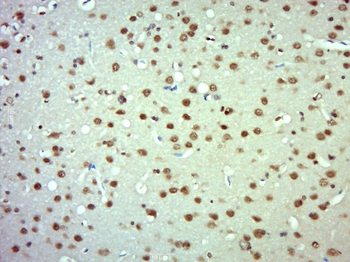

Antibody used in IHC on Human Intestine at 4.0-8.0 ug/ml.

Antibody used in IHC on Human Skin at 4.0-8.0 ug/ml.